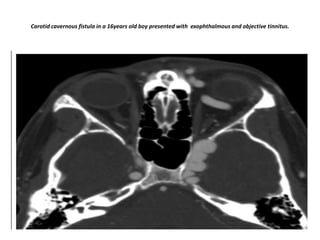

Carotid cavernous fistula in a 16years old boy presented with exophthalmous and objective tinnitus.

MRA demonstrate right carotid cavernous fistula(Arrow) with dilated superior ophthalmic vein